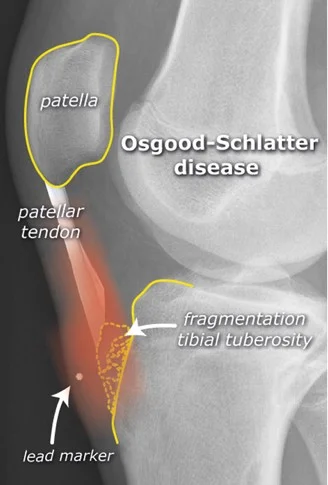

Traction Apophysitis

- Osgood Schlatter